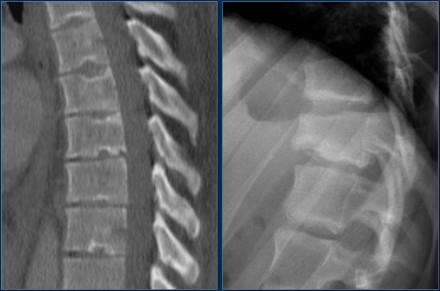

The images show a compression fracture.

All we see is a cortical disruption in the upper anterior wall of the vertebral body and slight loss of height ventrally.

The posterior vertebral cortex is intact.

The sagittal reformatted image also shows the cortical disruption.

Notice that on a 2.5mm axial slice you can miss these fractures.

You have to look at the thin slices to detect such a subtle fracture.

Scroll through the images.

Notice the horizontal band of density, which is often described as sclerosis.

This density does not mean that it involves an older fracture that is already healing with sclerosis.

This is merely a sign of trabecular impaction in an acute fracture.

It is very common to see more fractures on imaging with CT and MRI than on the radiographs.

In this case the CT shows 2 fractures and the MRI shows 3 fractures.